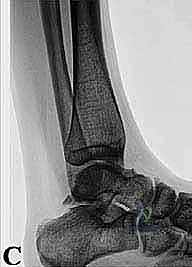

* الأشعة السينية (X-rays): بوضعيات خاصة (Lateral view) لرؤية العظم الزائد (Os Trigonum) والنتوءات العظمية وتضيق المسافات المفصلية.

* التصوير بالرنين المغناطيسي (MRI): هو المعيار الذهبي. يكشف بدقة متناهية عن التهابات الأوتار (مثل FHL)، ارتشاح السوائل، تمزقات الأربطة، ووذمة نخاع العظم (Bone Marrow Edema) التي لا تظهر في الأشعة العادية.

* الأشعة المقطعية (CT Scan): تُستخدم في حالات معينة لعمل خريطة ثلاثية الأبعاد للكسور القديمة أو التكلسات العظمية المعقدة قبل الجراحة.